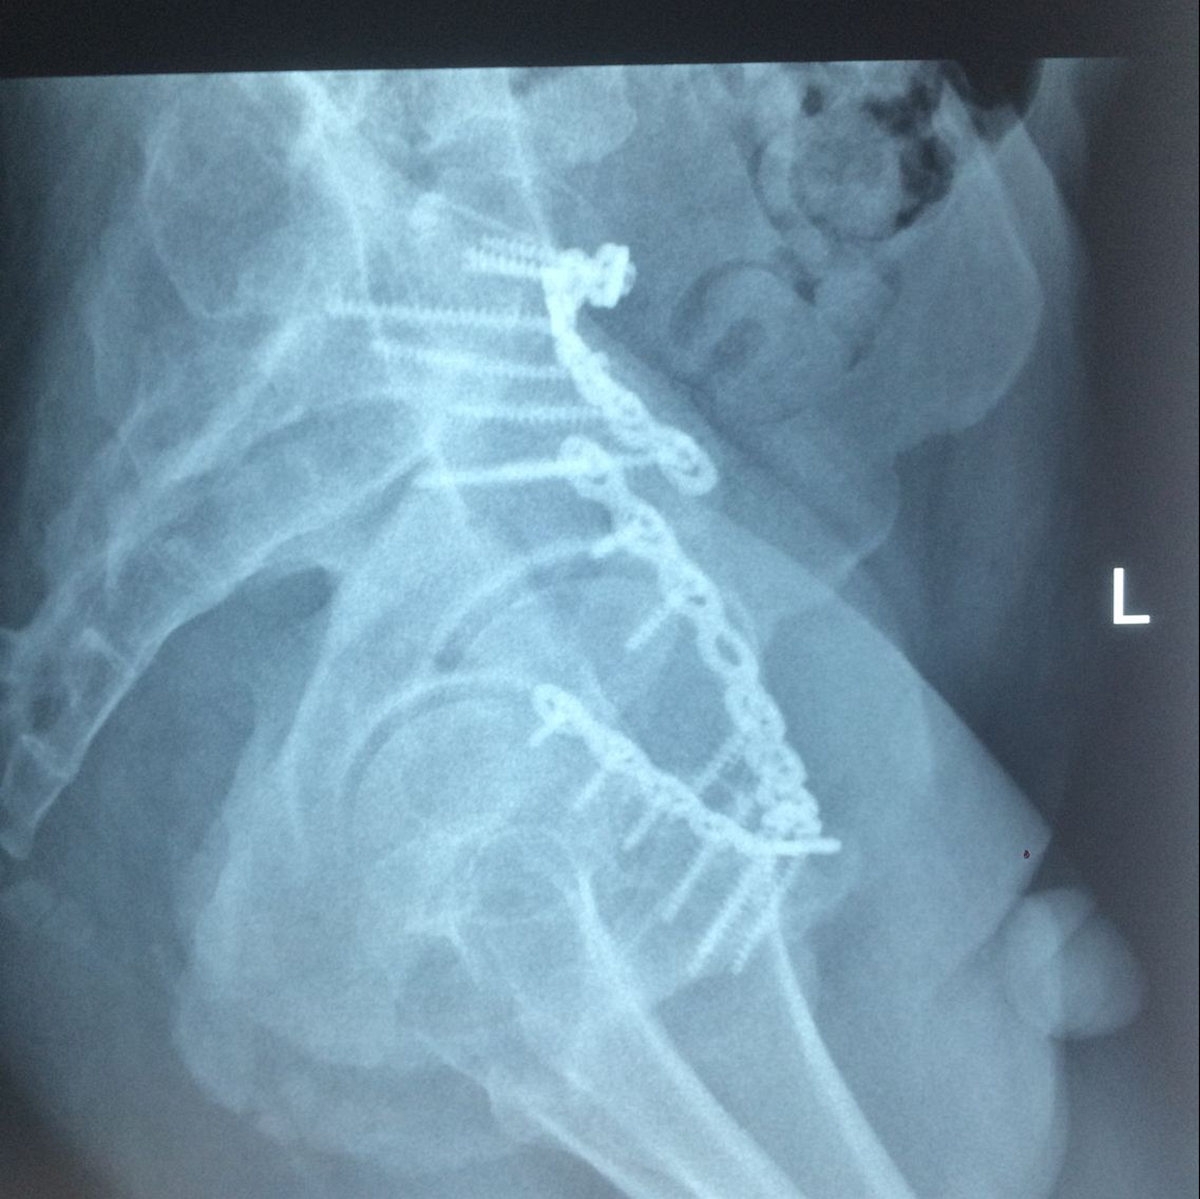

患者術(shù)后復(fù)查X片情況

術(shù)后X片